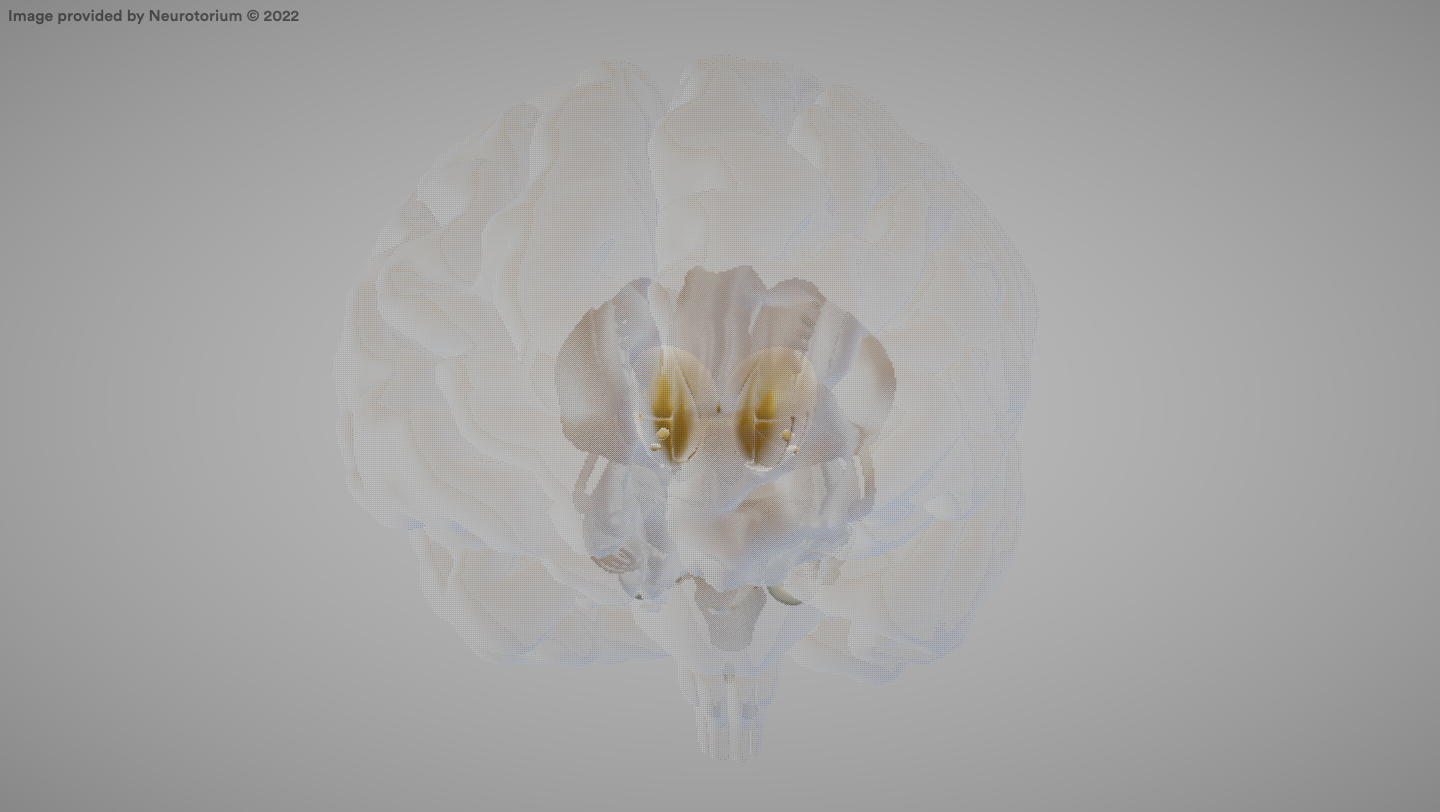

Basal Ganglia

A group of structures linked to the thalamus in the base of the brain and involved in coordination of movement.

Globus Pallidus

Part of the basal ganglia involved in motor control.

Caudate Nucleus

Part of the basal ganglia involved in motor control and procedural learning.

Putamen

Part of the basal ganglia; involved in motor control and learning